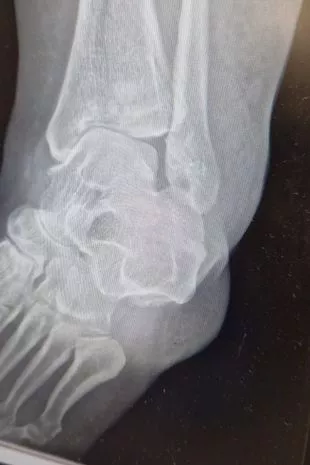

她补充说:“作为一名护士,我知道扭伤和骨折之间的区别。我听到了噼啪声。不仅仅是摔断了,我的腿都碎了。”她搭便车去了皇家普雷斯顿医院,在那里进行的X光检查显示,她的腿部和踝关节发生了皮隆骨折,需要进行手术。

第二天,她接受了手术。她补充说:“外科医生说这是一次严重的撞击伤,我的脚踝只是粉碎性的,腿上还有一些骨头——听起来太可怕了。”